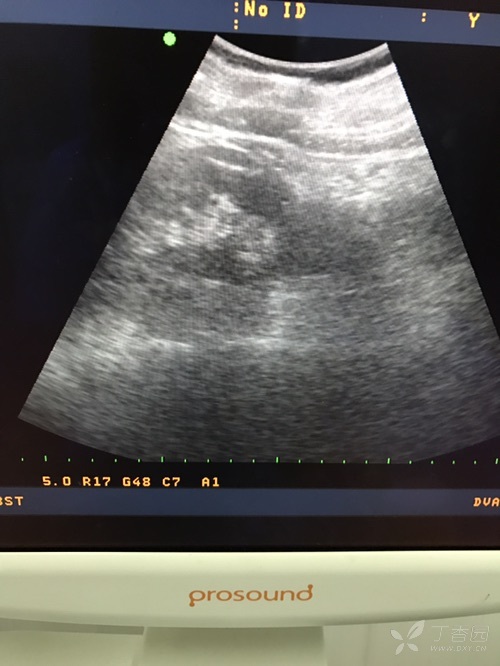

肾挫伤 - 超声医学讨论版 - 爱爱医医学论坛

图片尺寸720x576